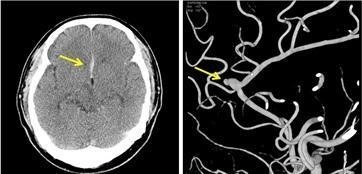

‘뇌혈관질환’ 중 뇌출혈 환자는 2007년 7만1,943명에서 2012년 8만493명으로 1.1배 증가한 반면 뇌동맥류 환자는 2007년 1만 2,446명이었던 것이 2012년에 3만 9,603명으로 3.2배 증가하였고, 인구 10만명당 환자수도 2007년 26명에서 2012년 80명으로 2007년 대비 3.1배 증가하였다.

양교수는 “뇌동맥류 환자가 늘어난 것은 질환 자체의 증가보다는 최근 들어 진단기술의 발달(MRI 등)로 기존에 진단하지 못했던 경우가 가능해졌기 때문으로 생각되며, 대개 뇌동맥류는 100명당 약 1명에서 발견된다고 알려져 있고, 뇌동맥류를 가진 환자의 1~2%정도에서 출혈을 일으키는 것으로 알려져 있다“고 설명했다.